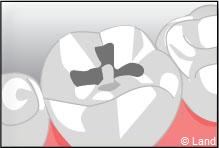

L’onlay intéresse aussi la surface occlusale (masticatoire) de la dent.

L’inlay-onlay reconstituera la dent comme la dernière pièce d’un puzzle. Il sera véritablement collé dans la dent.

Exemple d’un onlay molaire